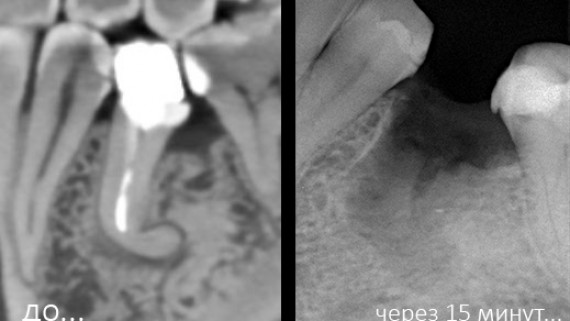

У меня нет вопросов по использованию коллагеновых матриц для изоляции графта во время консервации лунки после удаления. Во всех отношениях, это не противоречит ни здравому смыслу, ни заявленным свойствам Мукографта: